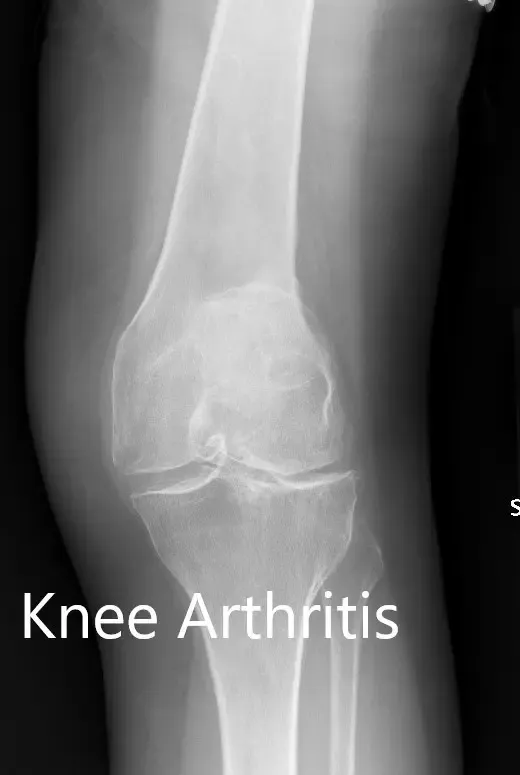

Los estudios de imagen realizados revelaron osteoartritis tricompartmental severa en ambas rodillas. Teniendo en cuenta que su estilo de vida limitaba el dolor de rodilla y el agotamiento de opciones conservadoras de manejo, le recomendaron un reemplazo bilateral de rodilla. Se le consideró candidato para un reemplazo total de rodilla personalizado. Él estuvo de acuerdo con el plan.

Radiografía preoperatoria que muestra la vista AP de la rodilla izquierda y la derecha respectivamente